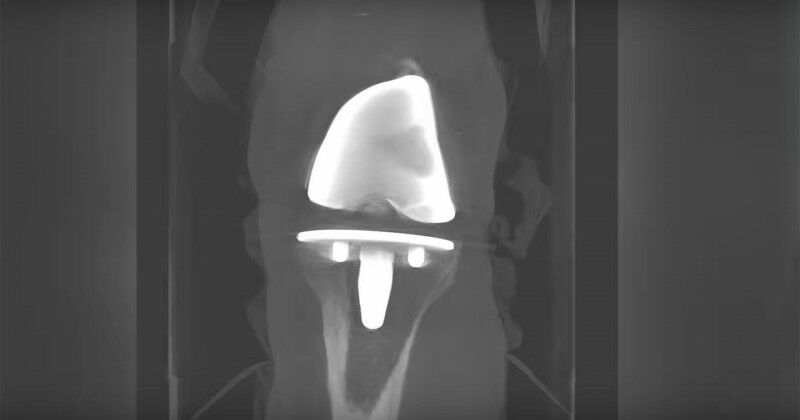

Imaging of a knee replacement (Lawson Health Research Institute)

Imaging of a knee replacement (Lawson Health Research Institute) New study: can probiotics can improve outcomes in knee replacement surgeries? Researchers are exploring how they can better support knee replacement patients' overall health Researchers at Western and Lawson Health Research Institute are examining whether the use of a daily probiotic can improve outcomes in patients who undergo total knee replacement surgery. There are more than 70,000 knee replacement surgeries in Canada each year, and up to 10 per cent of patients experience complications following the procedure. "One in five patients is dissatisfied after surgery due to pain and discomfort, and some patients need a repeat surgery because there is complication, infection or loosening of the joint," said Matthew Teeter , associate professor at the Schulich School of Medicine & Dentistry and scientist at Lawson Health Research Institute at London Health Sciences Centre (LHSC). Teeter and the research team are focused on improving patient outcomes. Recognizing that knee replacement patients who are considered healthy tend to have better outcomes, they are interested in how they can better support patients' overall health as one way to optimize their results. "The knee replacement patients I see in clinic are very diverse - from young, healthy, active patients to medically complex to socioeconomically disadvantaged," said Dr. Brent Lanting , Schulich Medicine & Dentistry professor, Lawson scientist and orthopaedic surgeon at LHSC.